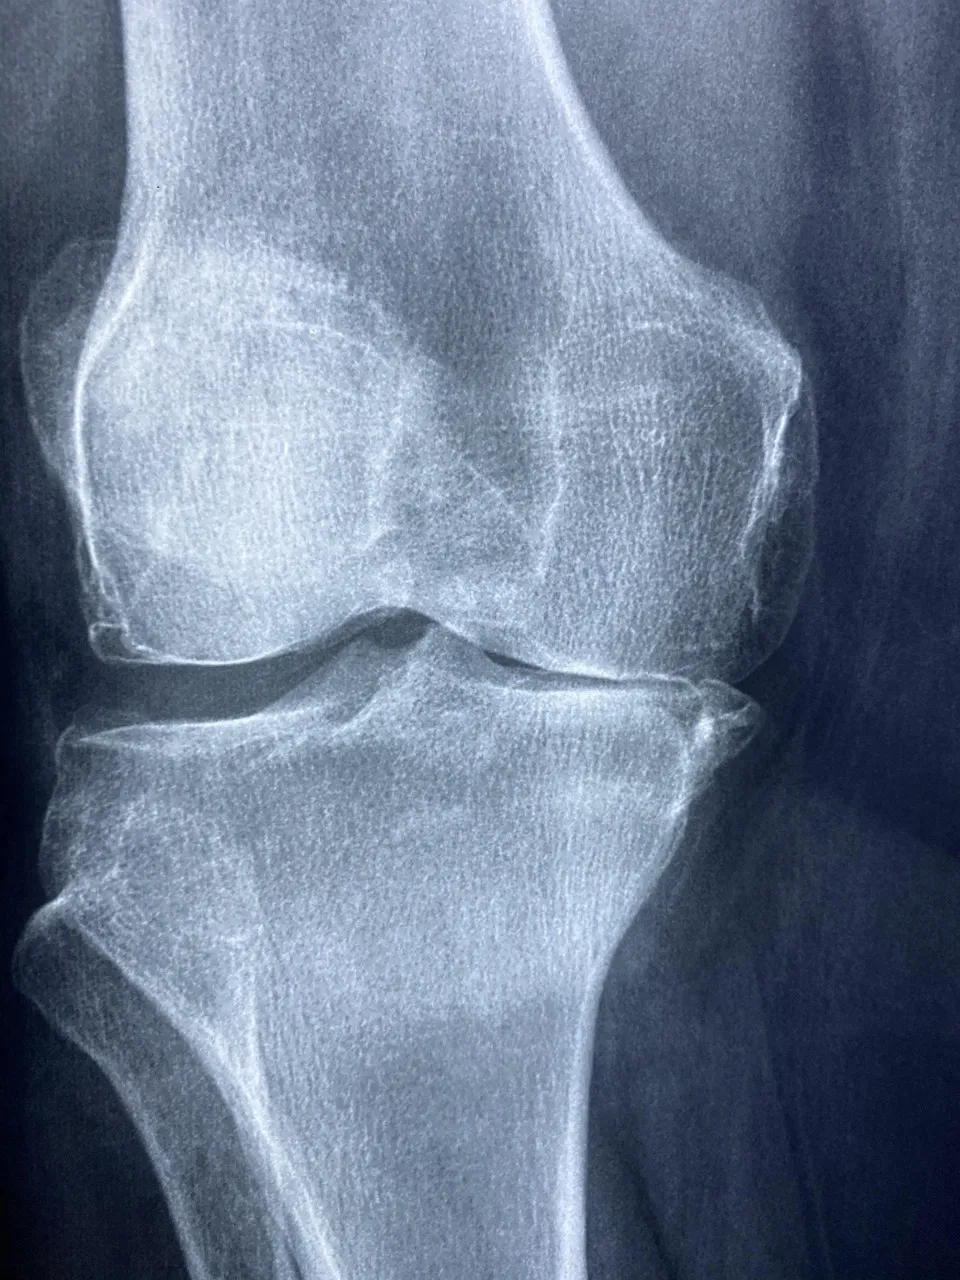

콘드로이친 효능 2 – 연골 보호 및 재생 도움

콘드로이친은 단순히 통증을 완화하는 것에 그치지 않고,

-연골 세포의 손상을 줄이고 재생을 돕는 역할도 합니다.-

부모님은 예전보다 무릎에서 ‘뻣뻣함’이 줄었다고 하셨는데,

이게 바로 콘드로이친 효능 덕분이라고 생각합니다.

특히 글루코사민과 함께 섭취하면 콘드로이친 효능이 더 잘 발휘된다고 알려져 있습니다.

콘드로이친은 연골 보호, 관절 윤활, 통증 완화, 피부 탄력 개선 등

여러 방면에서 건강에 도움을 주는 영양소라고 합니다.